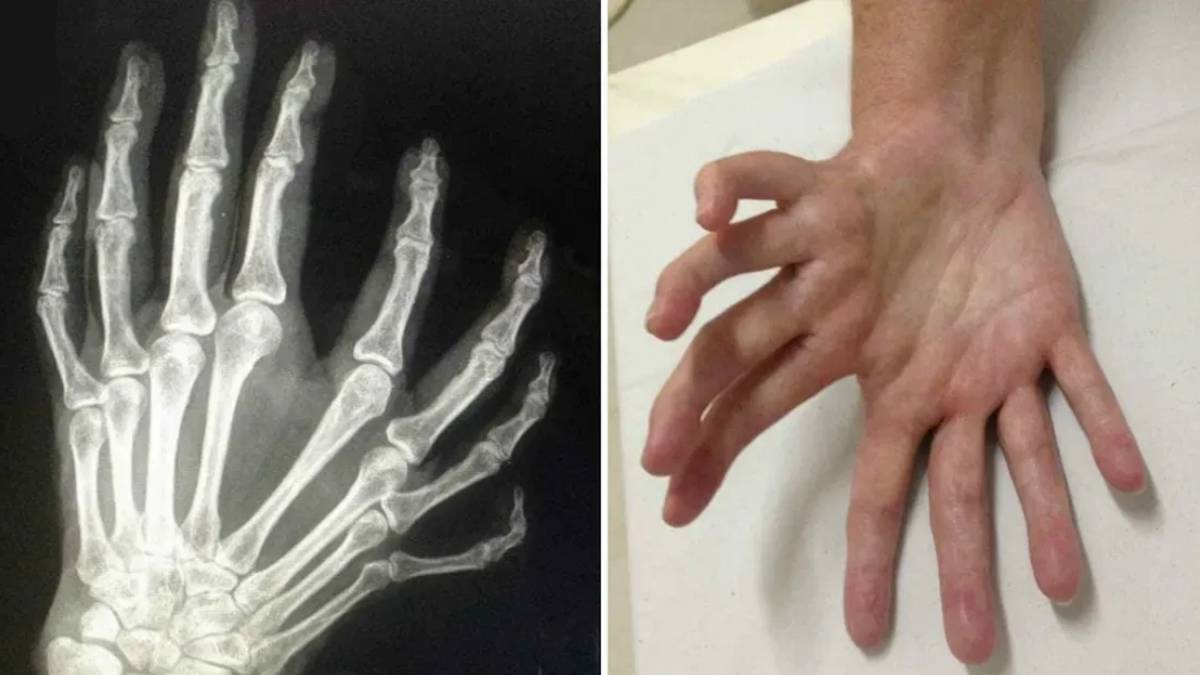

হাতের আঙুল না মাকড়সার পা? ধরতে পারবেন না! বিরল এই আট আঙুলের হাত দেখে চমকে ওঠেন চিকিৎসকেরাও...